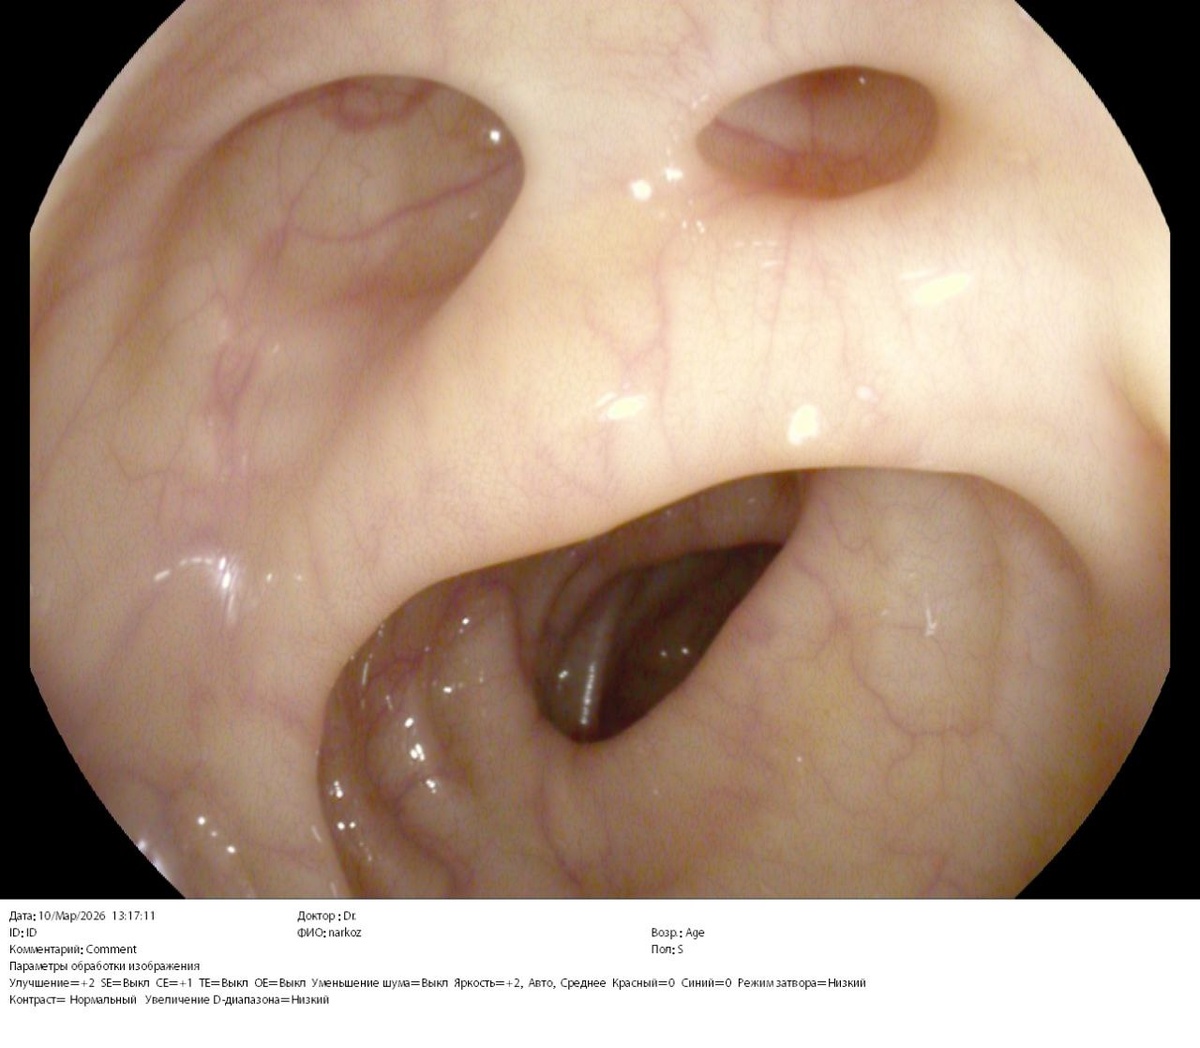

⚕️На фото множественные дивертикулы левой половины толстой кишки без признаков воспаления у пациентки 54 лет. Жалоб не предъявляет. «Случайная находка» при скрининговой колоноскопии.

✔️Итак, дивертикул - это грыжевидное выпячивание стенки полого органа.

Большинство дивертикулов толстой кишки (у 80% людей) остаются бессимптомными на протяжении всей жизни (дивертикулез), и диагноз часто ставится случайно во время колоноскопии, проводимой по другим причинам, например, для скрининга колоректального рака.

В отличие от этого, примерно у 20% развивается дивертикулярная болезнь, которая включает в себя множество клинических сценариев:

-✅️начиная от симптоматической неосложненной дивертикулярной болезни, характеризующейся рецидивирующими болями в животе, часто связанными с изменениями в работе кишечника и/или вздутием,

-✅️до острого начала симптомов и признаков (например, острая и сильная боль в животе, лихорадка и лейкоцитоз), характеризующих острый дивертикулит.

✔️Возникновение дивертикулов в стенке ободочной кишки, в первую очередь, обусловлено изменением механических свойств соединительной ткани подслизистого слоя. При этом действие внутрипросветного давления приводит к пролапсу слизистой оболочки через «слабые» участки кишечной стенки - места проникновения в нее кровеносных сосудов.